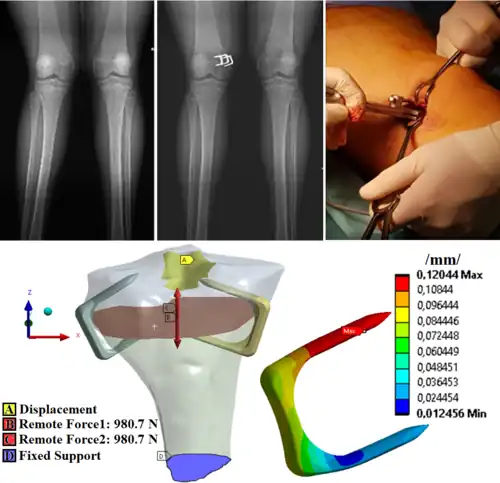

zevní fixace zlomeniny horní končetiny

Vnitřní fixace - design hřebu pro femur